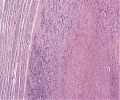

A92 Follikuläres Adenom der Schilddrüse

Randlicher Anteil mit mikrfollikulärem Aufbau (hohe Vergrößerung)

A92 Follikuläres Adenom der Schilddrüse

Randlicher Anteil mit mikrfollikulärem Aufbau (geringe Vergrößerung)